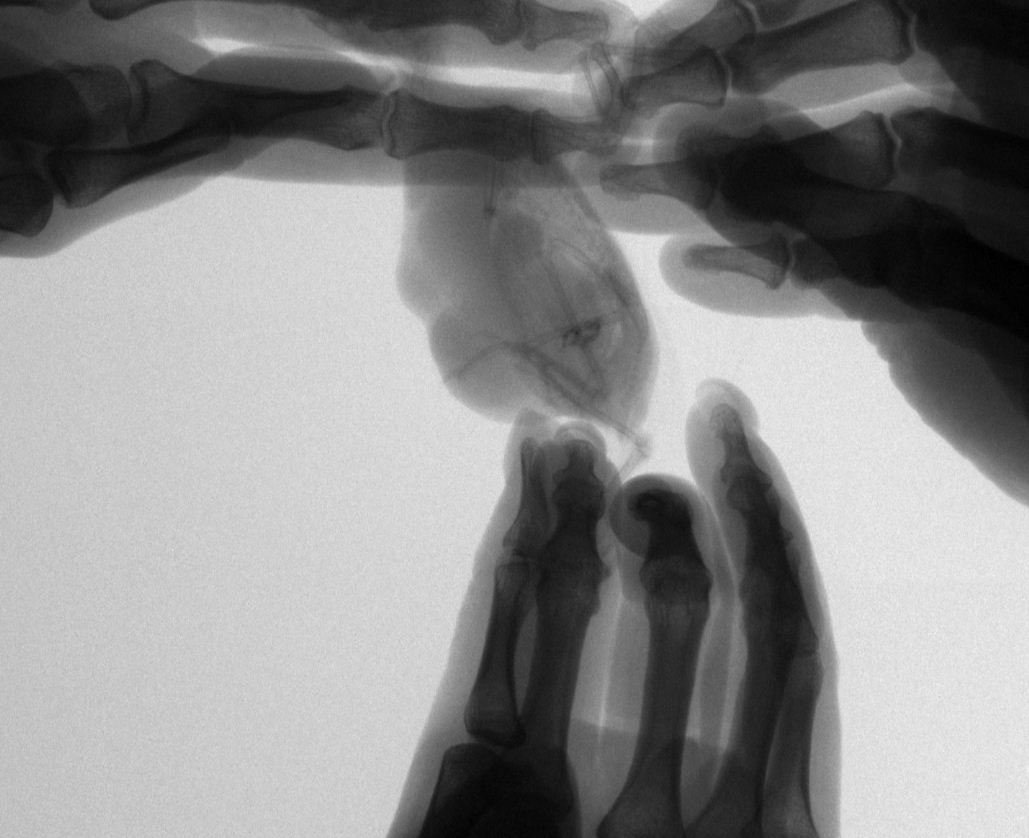

Вчера ездили на повторный рентген, спустя месяц лечения.

Врач сказал динамика положительная, по сравнению с предыдущими снимками.

Будем продолжать лечиться.

Рентген месяц назад ДО лечения